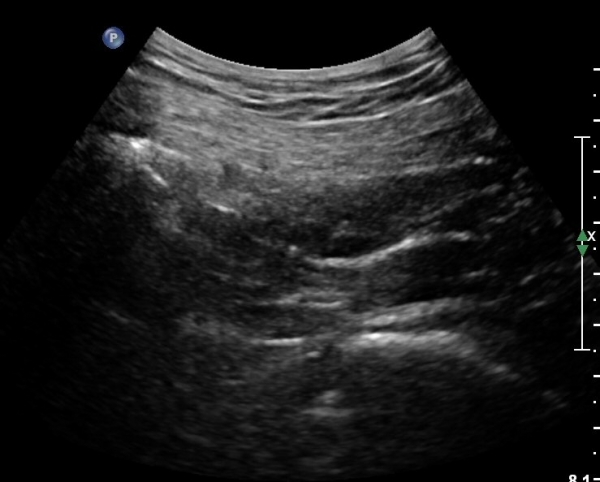

ŽÃÍÀÚ¸¦ ´Ù¸®ÂÊÀ¸·Î ¼öÆò À̵¿ÇÏ¸é ½ÉÃþ¿¡¼­ Àå°ñÀÌ »ç¶óÁö°í »õ·Î¿î ±ÙÀ°ÃþÀÌ º¸À̴µ¥ À̰ÍÀÌ ÀÌ»ó±ÙÀ̰í ÀÌ»ç±Ù ½ÉÃþ¿¡¼­ Á°ñ½Å°æ¸£ °üÂûÇÒ ¼ö ÀÖ´Ù(»çÁø 2, 3).